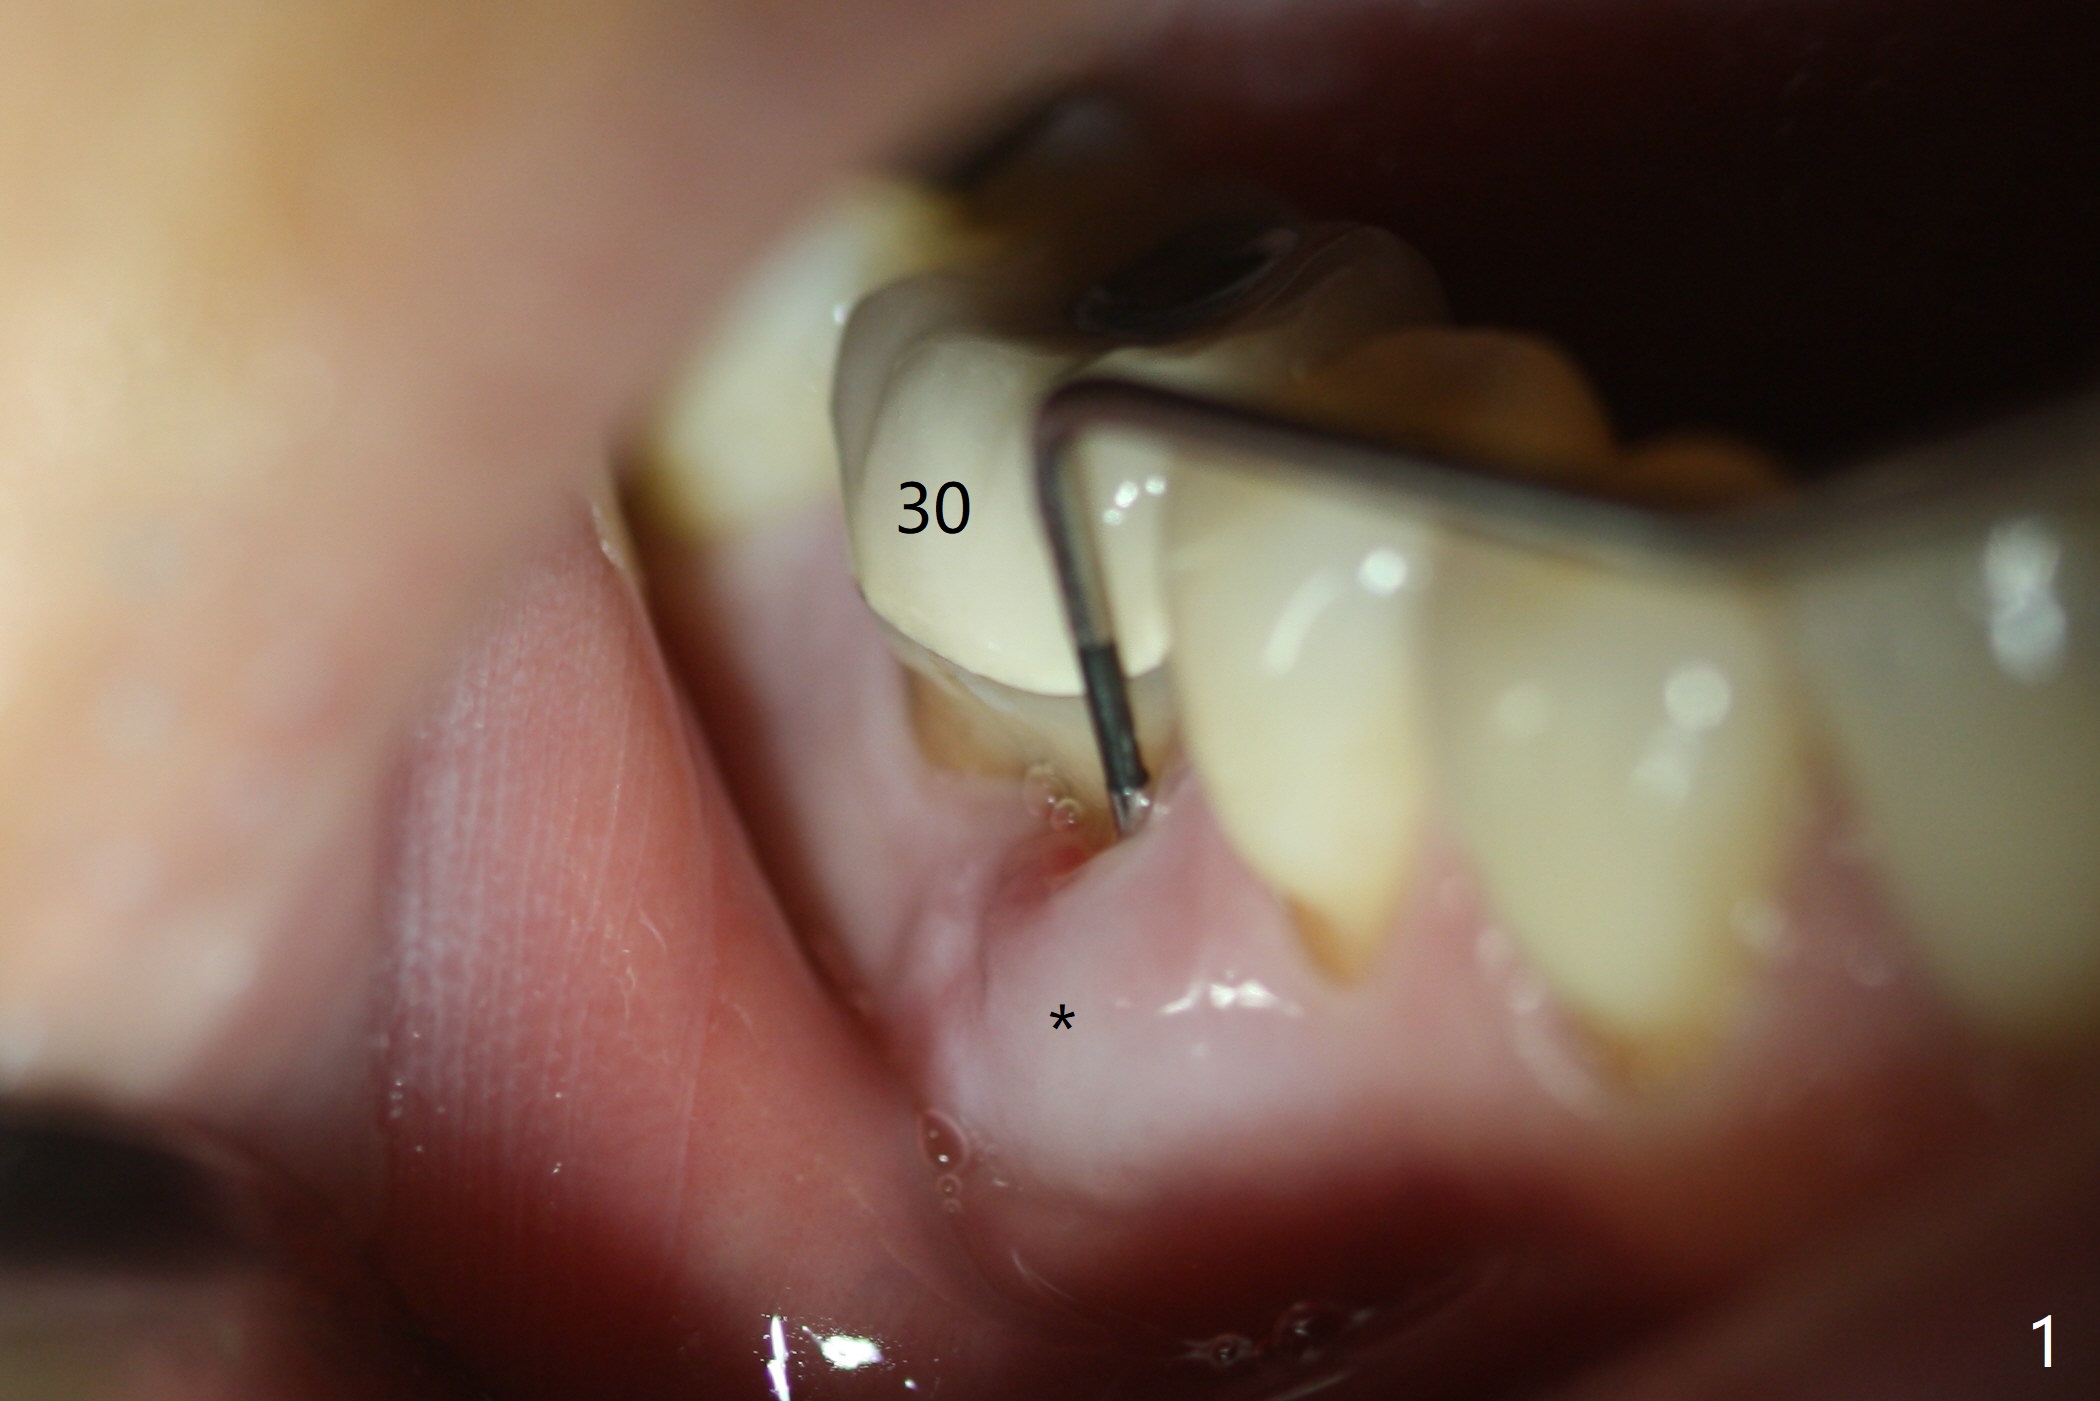

Preop oral Amoxicillin seems to be associated with reduction in the buccal and lingual (Fig.3 arrow) fistulae at #30, but there is mesiobuccal swelling (Fig.1 *) with 7 mm pocket (Fig.2). Osteotomy is initiated in the middle of the septum (Fig.3-5 S). As the osteotomy increases, it shifts mesially (Fig.6 arrow). Guided surgery is able to reduce shifting. A 5x13 mm implant is not seated completely (Fig.7) apparently due to osteotomy shifting. After removal of the bone from the osteotomy distally, the implant remains unseated with lower torque value (Fig.8). Following reuse of the 4.3 mm drill deeper by 1-2 mm, the implant is seated to a satisfactory depth (Fig.9 with increase in torque to 50 Ncm) with placement of Vera Graft (*) and a 7.5x4(3) mm abutment. After a second round of allograft placement (Fig.10 *), the implant is found to be 4 mm from the IAC. At the later stage of osteotomy, the coronal end of the septum is destroyed with loss of osteotomy depth landmark. It is apparent that the soft tissue landmark may be more reliable. The implant threads appear to be covered by the bone graft 3.5 months postop (Fig.11). The abutment is changed to 6.5x5(3) mm one before impression with minor margin prep. The bone density seems to increase 5 months postop, i.e., immediately post cementation (Fig.12) and 10 months postop (5 months post cementation (after retightening abutment), Fig.13 (*)). Periimplantitis develops mesiobuccally, consistent with bone loss 1 year 7 months post cementation (Fig.14 *); the implant seems to have been buccally placed. Bone graft is necessary with PRF or GEM21S if the vein is small and 6-month membrane with a hole around a 7.5x4(4) cemented abutment for easy wound closure. Take 5x5 CM CBCT to determine which wall has defect, buccal or lingual. Check mesial contact. If so, remove the crown, reseat the abutment (possible incomplete seating) and re-impress after bone graft.